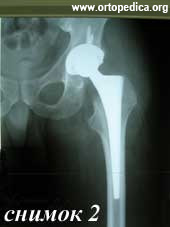

Пример №20 Ассептический некроз головки бедренной кости

2. После операции